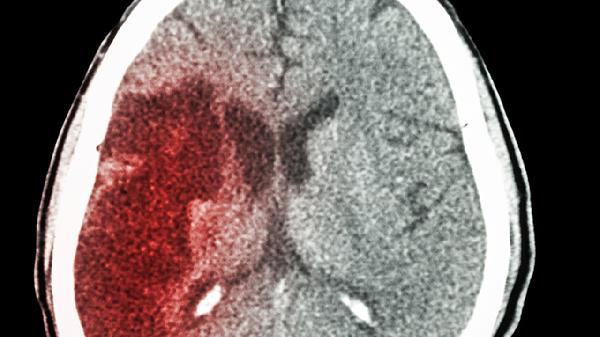

少数情况下,若宝宝摔落后出现喷射状呕吐、持续哭闹不安、瞳孔大小不等或肢体抽搐,需警惕颅内出血或脑震荡。婴幼儿硬膜下血肿可能表现为前囟门膨隆、面色苍白等非典型症状。此类情况须立即平卧固定头部送医,途中避免喂食以防误吸。颅脑CT是确诊颅内损伤的主要手段,婴幼儿需在专业儿科神经外科评估后决定是否需手术干预。